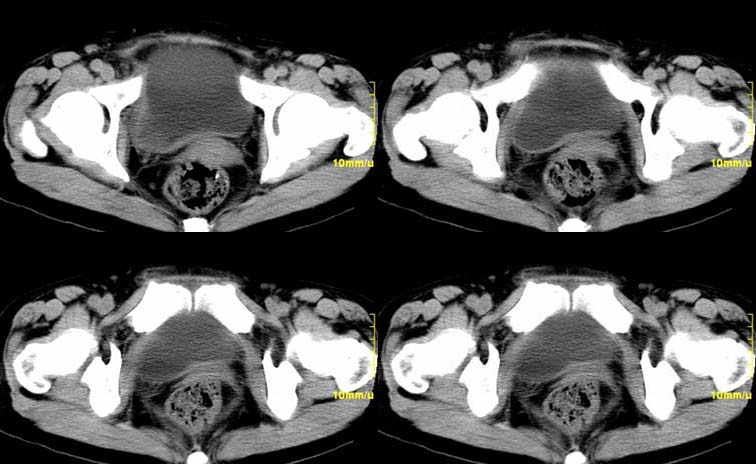

患者,52,右下腹疼痛一月,当时有发热,抗炎治疗20余天,至今仍疼痛,且有低热。

增强

右附件区软组织包块,内可见坏死,边界不清,周围软组织及脂肪组织可见密度增高,膀胱右侧壁增厚,并且呈膨胀不全的改变,考虑炎性包裹,不知道有没有手术史??

右侧附件见一肿块,边缘与周围组织分界不清,增强扫描见肿块明显强化,越到后期强化越明显,中央见坏死,内壁光整,与临近子宫壁、直肠及膀胱后壁均见炎症波及。这种厚壁肿块、内缘光整外缘模糊、增强扫描强化越后越强是附件脓肿典型的ct表现。

右侧卵巢输卵管慢性脓肿,炎症波及临近子宫、直肠及膀胱形成粘连。

右附件区软组织包块,内可见坏死,边界不清,周围软组织及脂肪组织可见密度增高,膀胱右侧壁增厚,并且呈膨胀不全的改变,考虑炎性包裹